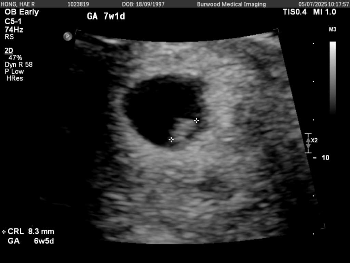

7주1일차에 갔는데 6주 5일로 바꼈네요 애기 심장도 잘뛰고 128bpm 너무 신기했어요 아무 문제없이 잘 크면좋겠네요🥹 해외살고있어 그다음 초음파는 12주차에 본다네요..허허 어케 기다리죠..